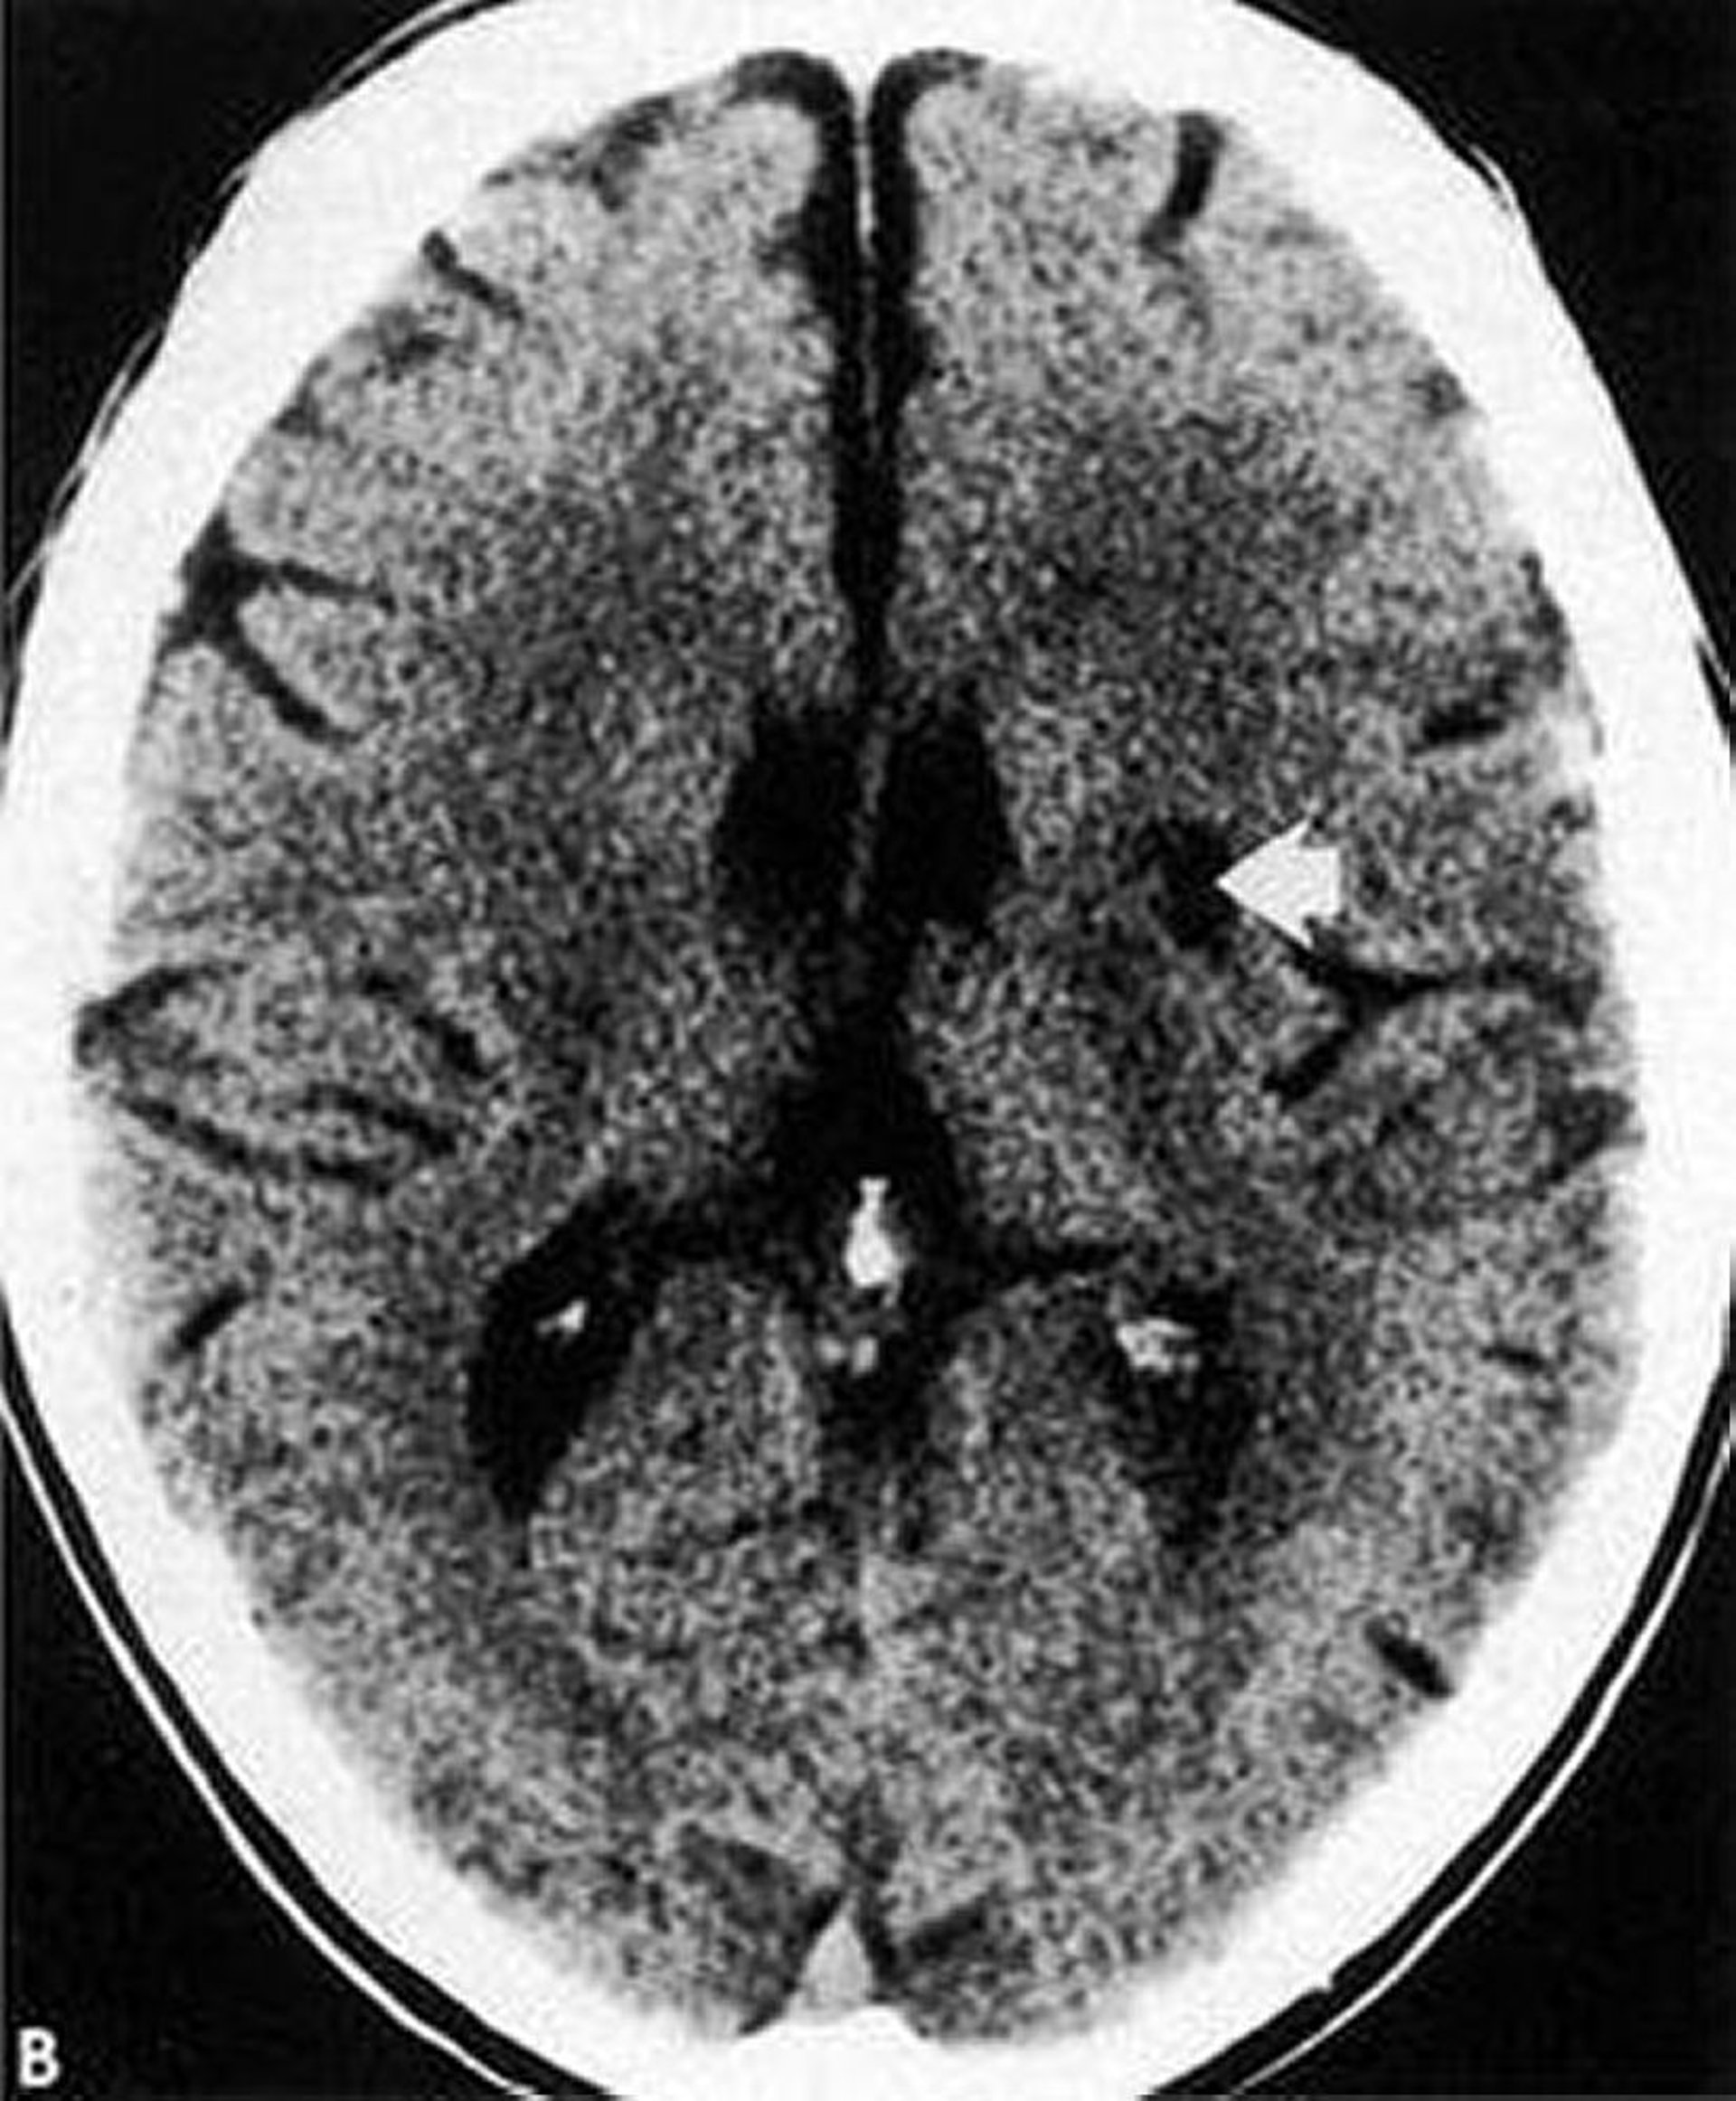

Nhồi máu ổ khuyết

Chụp CT này cho thấy nhồi máu ổ khuyết giảm âm, bờ rõ (mũi tên) trong hạch nền.

Được sự cho phép của nhà xuất bản. Theo Geremia G, Greenlee W. Trong Atlas of Cerebrovascular Disease. Biên tập bởi PB Gorelick và MA Sloan. Philadelphia, Current Medicine, 1996.